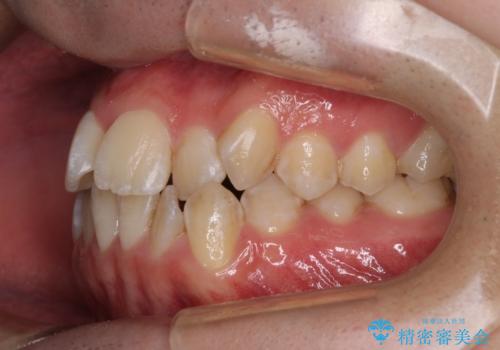

- 上下前歯のデコボコを気にして来院された患者様です。

ワイヤー矯正でもマウスピース矯正でも可能でしたが、短期間で、自身の手を煩わせることなく治療を行いたいとのことで、ワイヤー装置にて矯正治療を行うこととしました。

当初予定通り、1年間で治療を終えることができました。